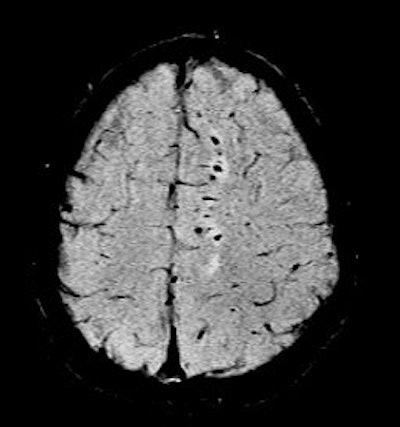

In traditional diffusion-weighted imaging (DWI) for stroke, "you'd look at this for cellular disruption, and you'd see quite clearly the major region affected by the stroke," he said. "DWI is often very broad. In the SWI image, you are seeing evidence of dramatic changes in oxygen saturation and maybe other sources of susceptibility. We can see the source of the stroke and maybe the vascular territory affected (see below). The hypothesis is that the deoxyhemoglobin content of the small vessels has increased over their normal values due to slower or restricted flow, making these (vessels) visible when they would normally not be visible."

| Stroke imaging with SWI. Although the DWI image (above) shows the affected region well, the details of the stroke are shown in the SWI image (below). Images courtesy of Dr. Daniel Wycliffe, Loma Linda University, Loma Linda, CA. |